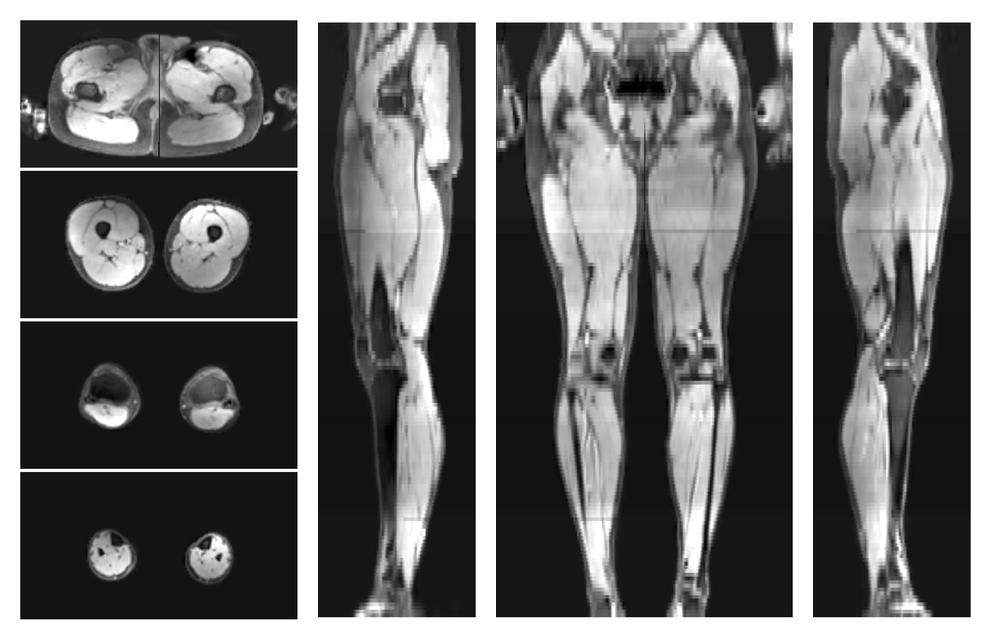

• Fat fraction

The fat fraction of the lower extremity obtained from the dixon reconstruction for muscle water fat quantification.